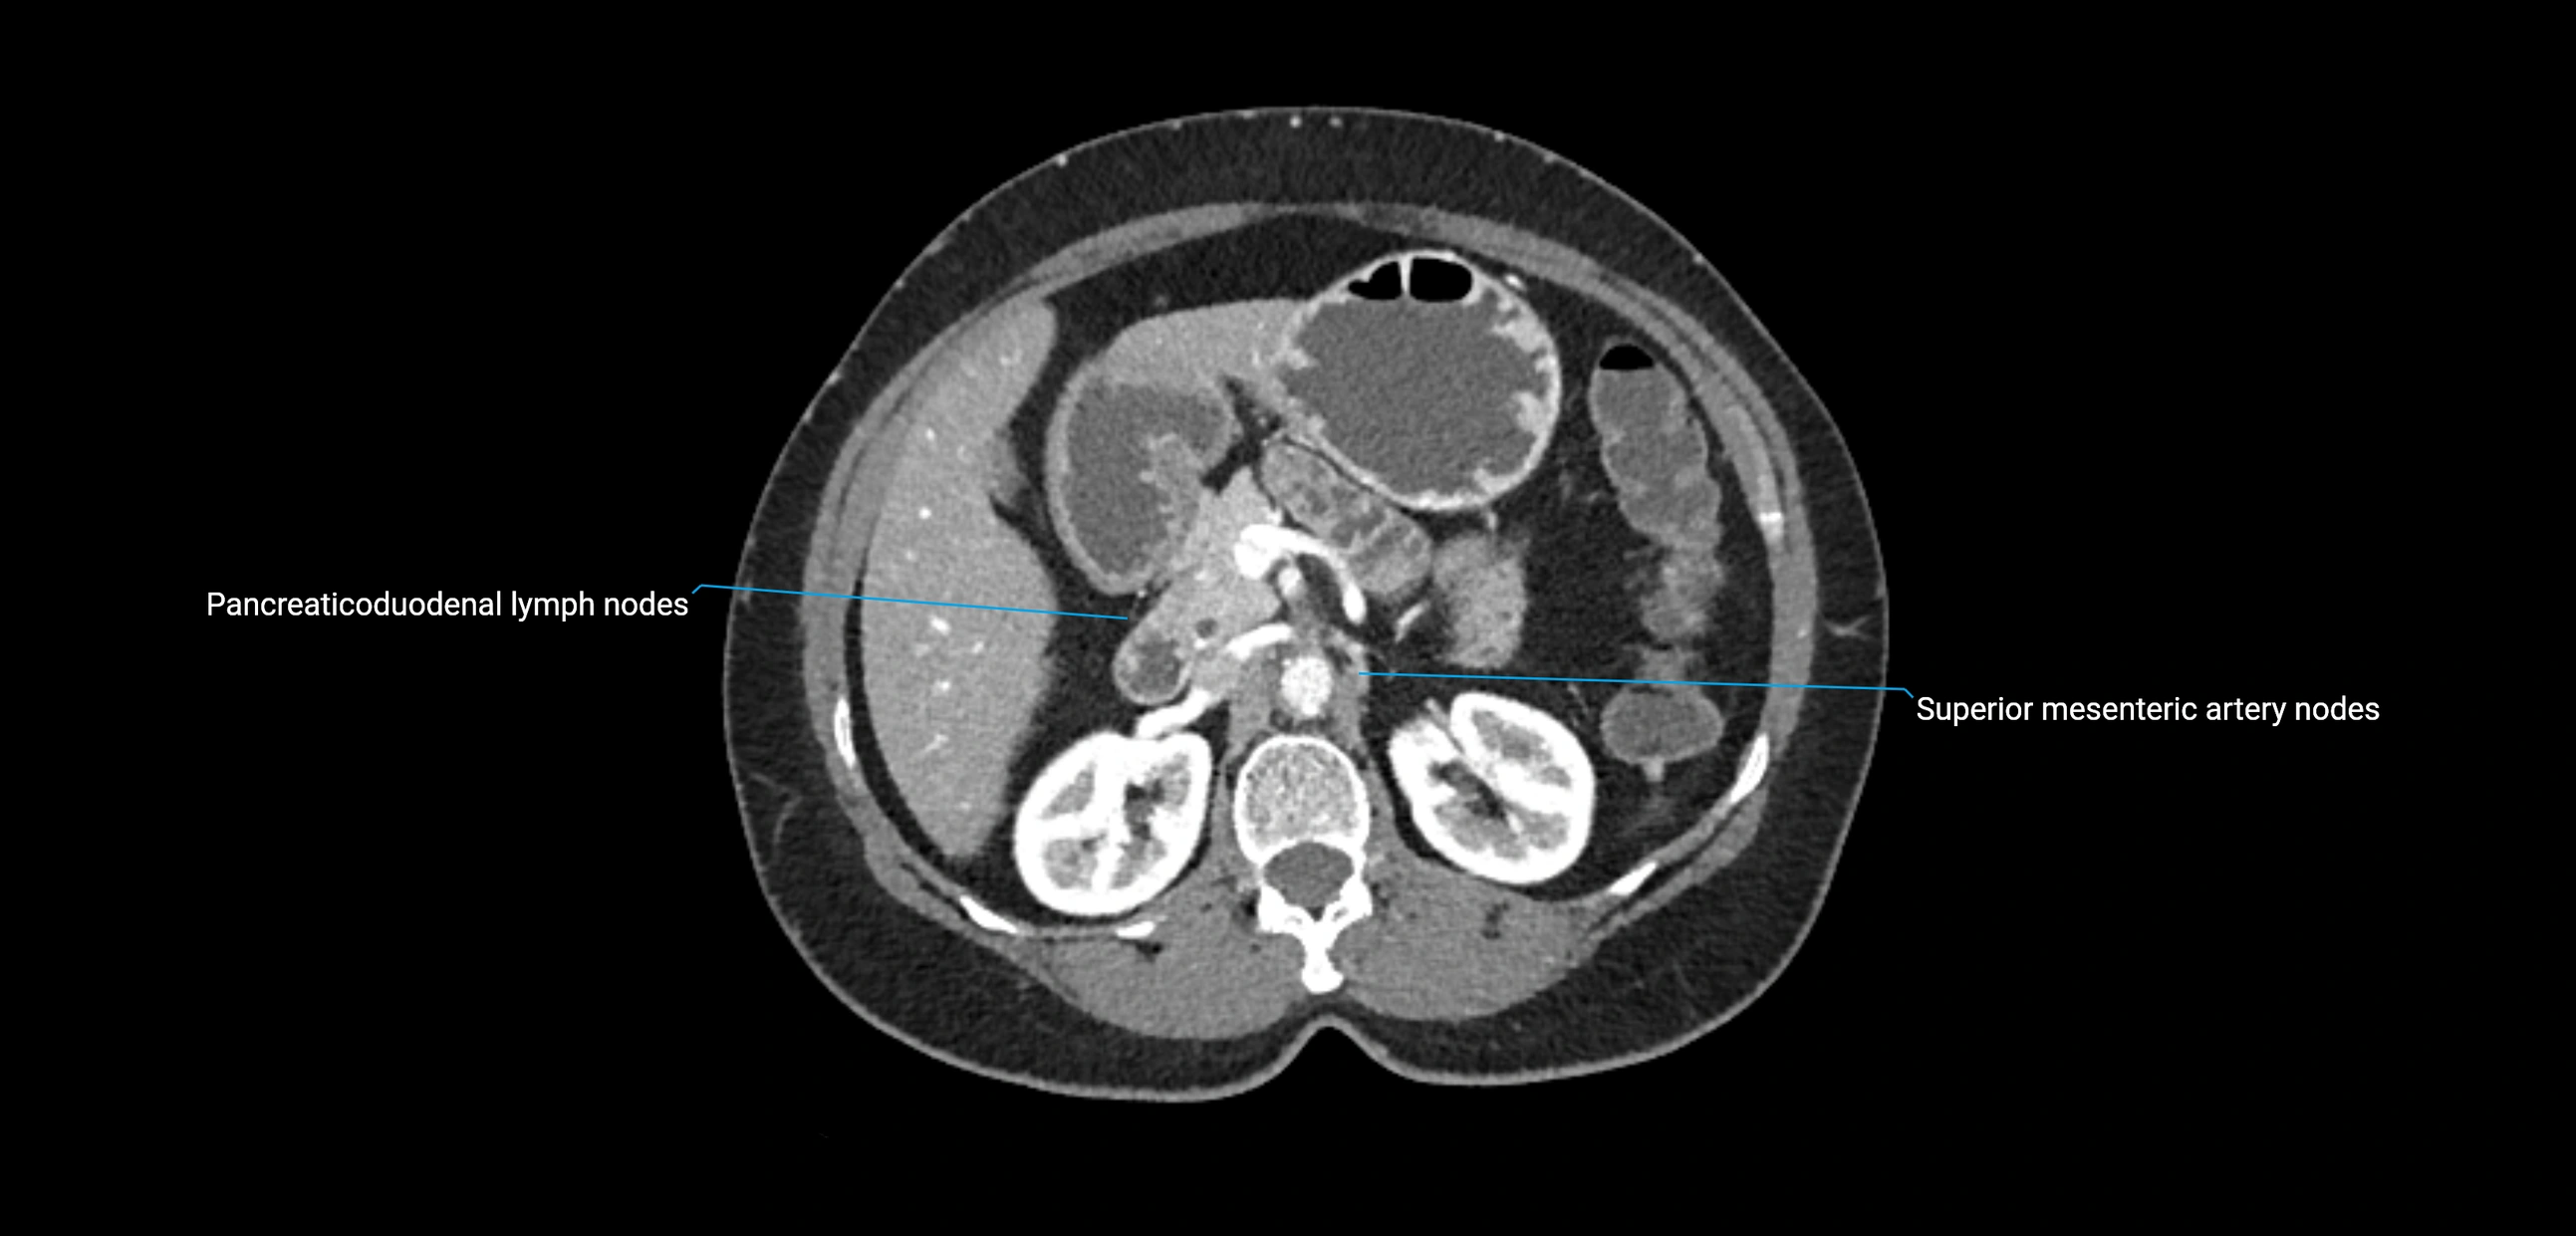

CT Appearance

CT Pre-Contrast:

• Nodes appear as soft-tissue density nodules adjacent to the aorta and IVC

CT Post-Contrast:

• Normal nodes enhance homogeneously

• Malignant nodes may show heterogeneous enhancement, central necrosis, or conglomerate formation

• Size >1 cm short axis is suspicious, though morphology and distribution are equally important